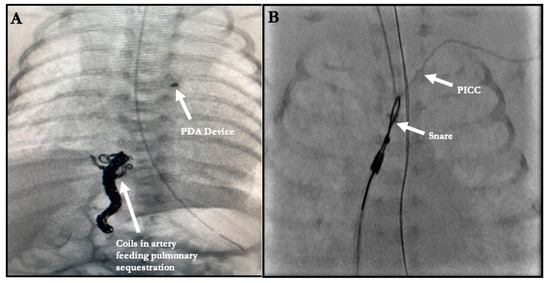

| 8. Coiling of artery to pulmonary sequestration | 2 |

| 8. Coiling of artery to pulmonary sequestration œ | 2 | 0 | 0 | 2 |

| 3. Foreign Body Retrieval | 8 |

| 3. Foreign Body Retrieval ^ | 8 | 0 | 0 | 8 |